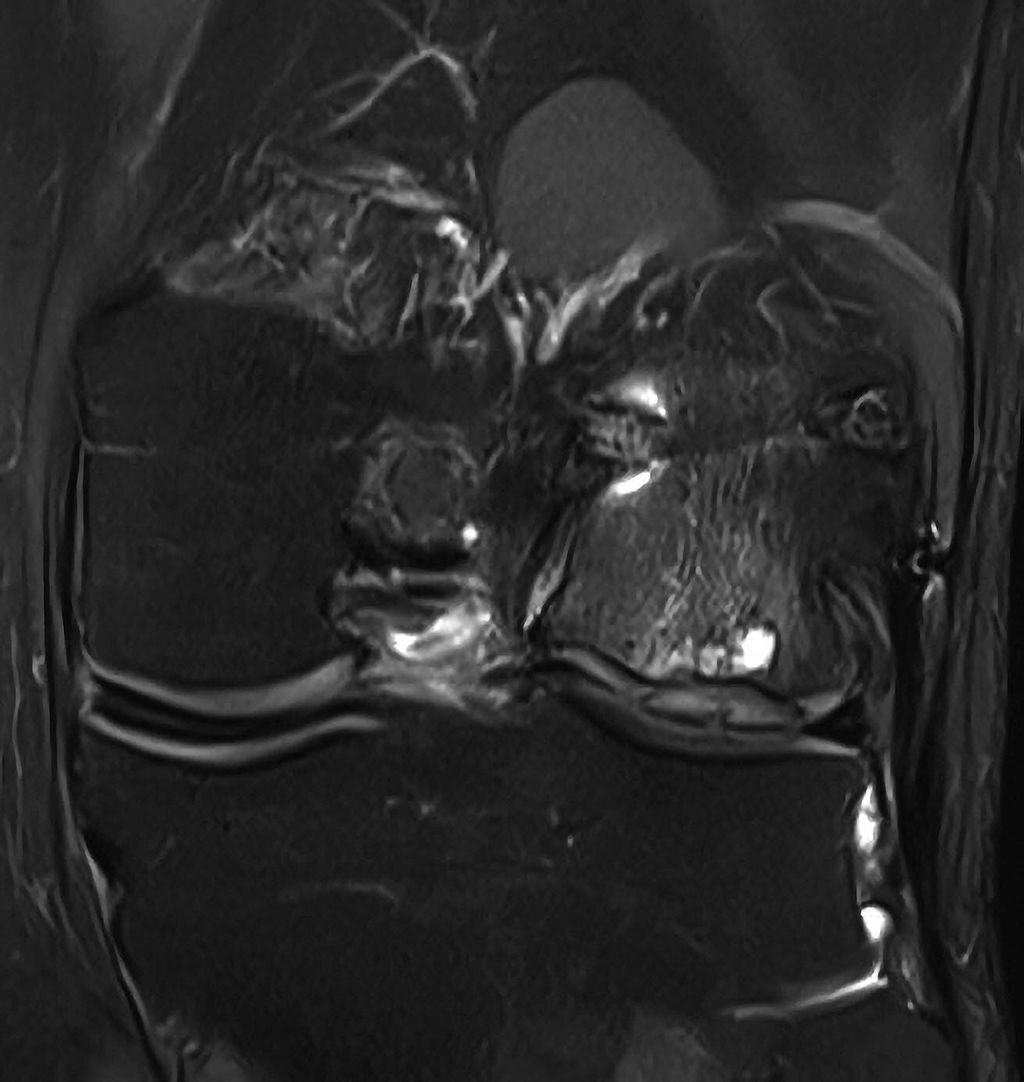

Abb. 1: Hypertrophie des Knorpelregeneratgewebes am lateralen Femurcondylus nach MACT (matrixgekoppelte autologe Knorpeltransplantation) mit subchondraler Zystenbildung

Abb. 2: Das arthroskopische Korrelat des MRT-Bildes zeigt ein instabiles Knorpelregenerat mit fehlender Integration und beginnender Delamination